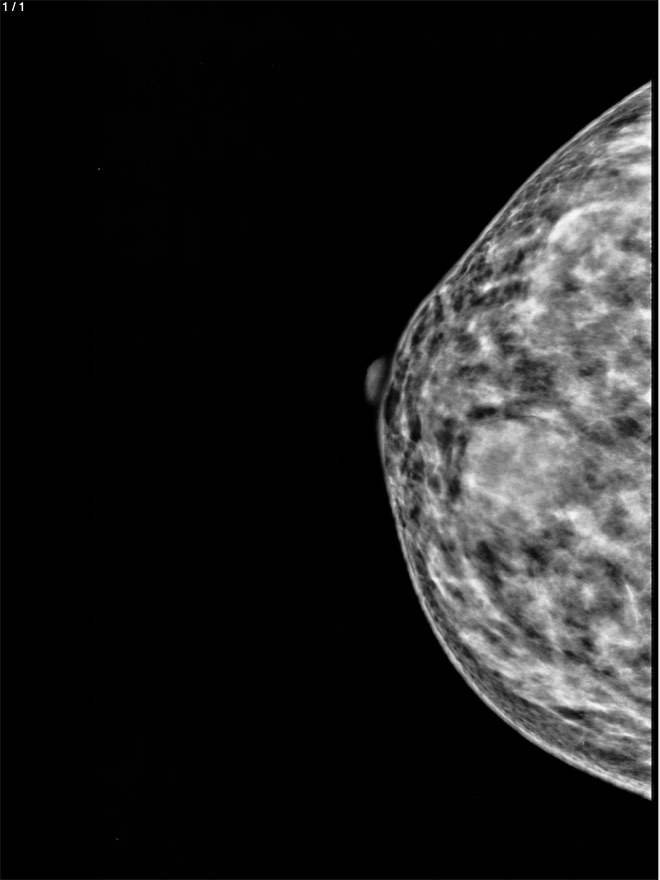

Teresa Garcia Garcia - Unnamed